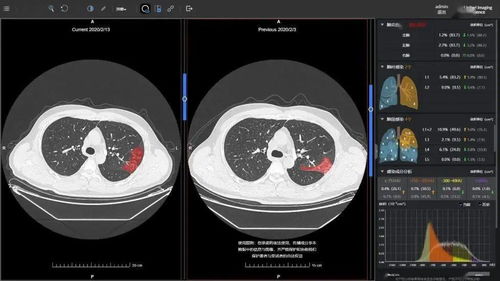

胸部诊断:如肺炎、肺结核、肺癌等。

图像质量:通过改进X射线源和探测器技术,CT系统的图像质量得到了显著提高。

人工智能辅助诊断:利用人工智能技术,提高CT图像的解读准确性和效率。